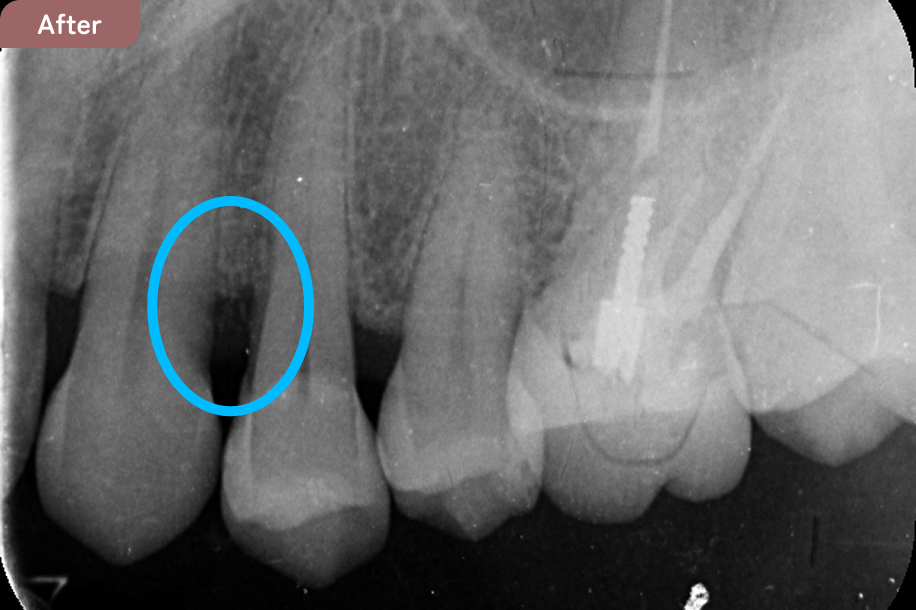

青丸の部分に再生療法を行った結果、骨の再生が認められる。